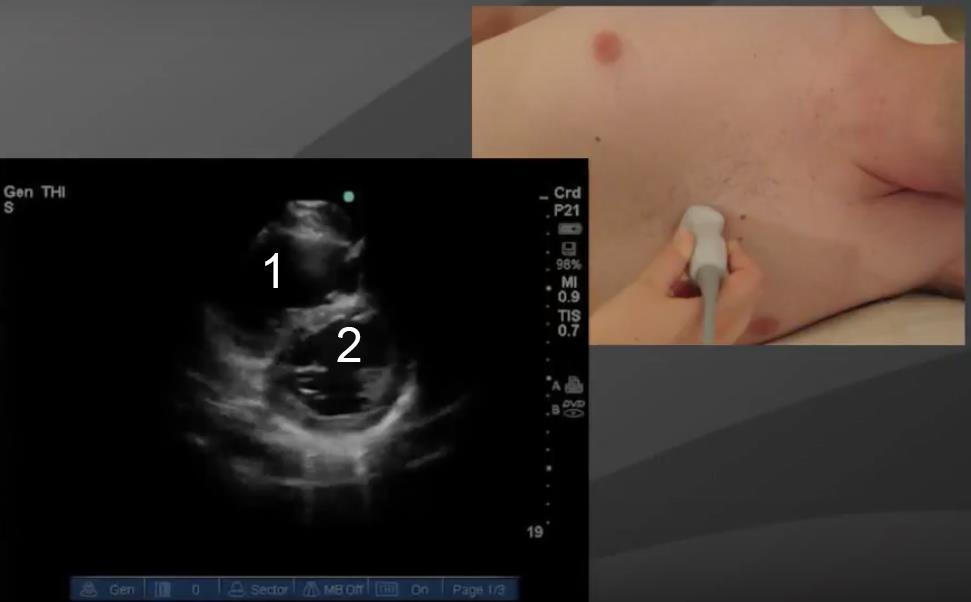

Heart Parasternal Short Axis (PSAX) Image

Right Ventricle (RV)

Left Ventricle (LV)